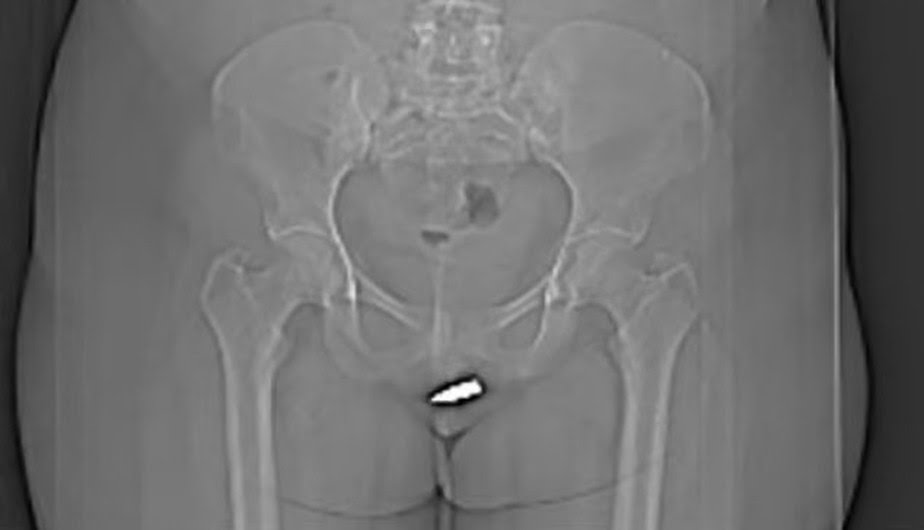

Após a realização de uma tomografia computadorizada, que confirmou a localização da bala, a paciente passou por uma cirurgia. Segundo a publicação, não foram observadas complicações depois que o procedimento foi feito. No dia seguinte, a mulher teve alta em “boas condições”.